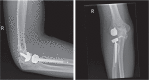

Primary radial head arthroplasty (RHA) produces good or excellent results in approximately 85% of patients. However, complications are not uncommon and have been described in up to 23% of cases.The number of RHA is increasing, and consequently the absolute number of complications is expected to rise as well. The decision on whether to revise or remove the prosthesis seems more likely to depend on the preference of the surgeon or the hospital, rather than on objectifying problems with the prosthesis.The current article presents an algorithm for the work-up and treatment of most complications that can occur following RHA.Five subgroups of problems were identified: osteoarthritis, stiffness, instability, infection and implant-related issues.In short, the preferred treatment depends mainly on the chondral condition and stability of the elbow joint. Cite this article: EFORT Open Rev 2020;5:398-407. DOI: 10.1302/2058-5241.5.190055.